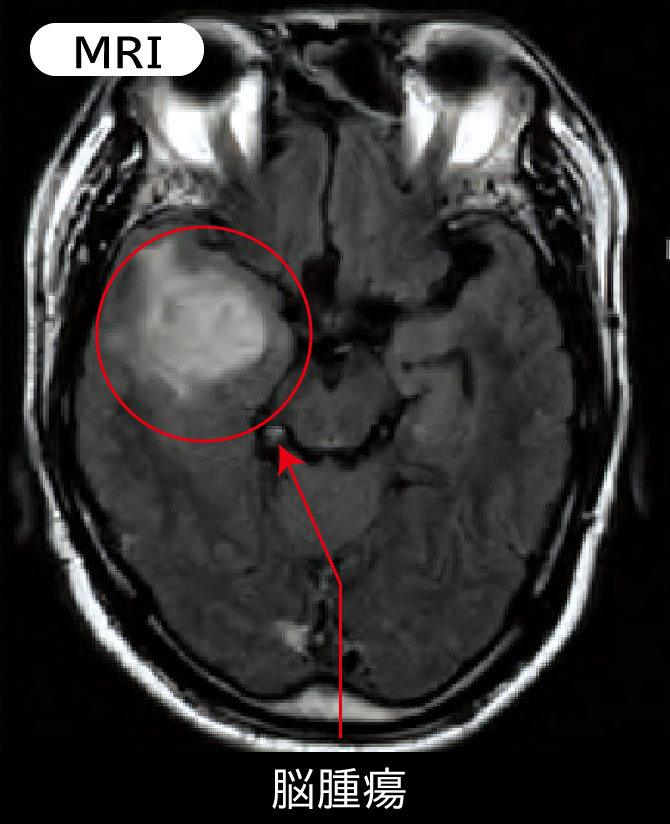

MRI・MRA検査は、X線を使用せず、強力な磁場を利用して頭部を撮影します。脳の断層写真を撮影し、脳腫瘍や脳梗塞を鮮明に写し出す「MRI」、脳の血管を立体的に写し出し、血管が狭くなっているところや脳卒中の前兆を発見する「MRA」という2種類の検査があります。MRAは、MRIとセットでお受けいただく必要があります。